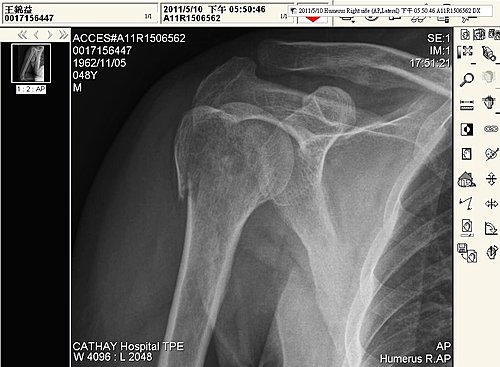

2011.05.10 拍攝的X光圖